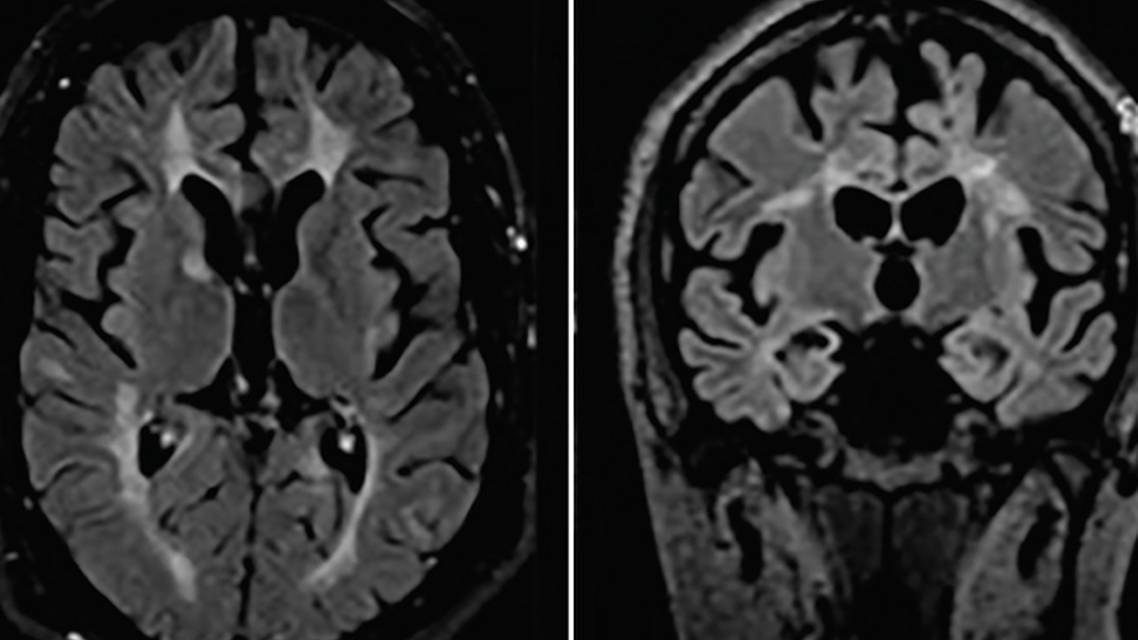

At age 35, Mr. L was diagnosed with MS after he presented with diplopia and his brain MRI findings showed demyelinating lesions in the brain (Figure 1), cervical, and thoracic spinal cord as well as unmatched oligoclonal bands in his cerebrospinal fluid. At that time, his diplopia improved spontaneously and he was started on fingolimod to treat his MS.

By age 40, Mr. L’s tremor was reportedly worse and he complained of a decline in dexterity of his right hand with reduction in size of his handwriting and worsening gait. His neuroleptics had been discontinued. Brain MRI findings then showed new demyelinating lesions with discontinuous rim enhancement in the left globus pallidus, left frontal centrum semiovale, and right periatrial white matter MRI (Figure 2A-D).